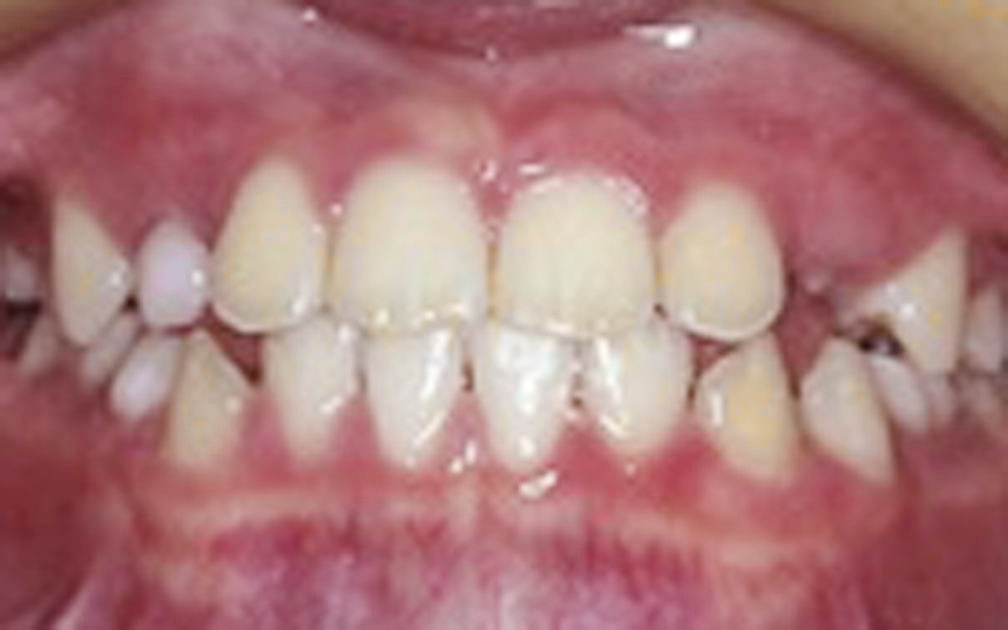

矯正の症例3 (診断名)叢生(ソウセイ)

(患者様の主訴)八重歯が気になる

(治療開始年齢)23歳4カ月

(主な治療装置)エッジワイズアプライアンス

(抜歯部位)上下第1小臼歯4本抜歯

(治療期間)1年10カ月

(治療費)¥805000

(個別リスク・副作用)叢生が著しいため動的治療後長期にわたる保定が必要となる。

歯牙の移動量が大きいため歯根が短根になるリスクがある。

叢生が改善されるまで、ブラッシングがしにくい状態が続くために齲蝕になるリスクがある